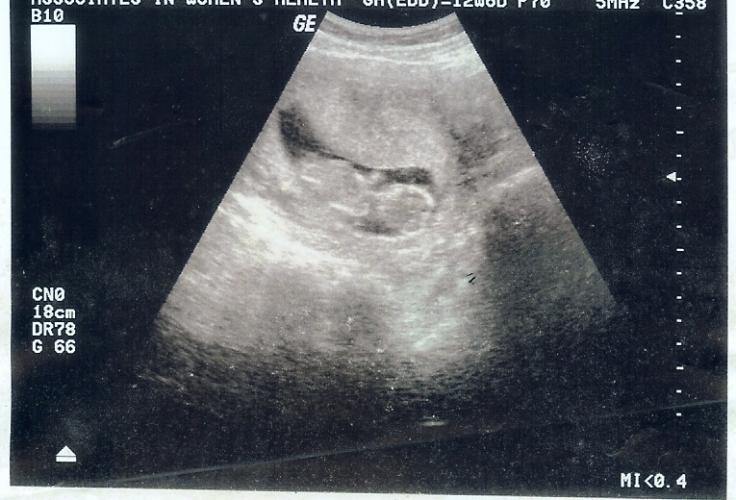

Ultrasound showed it's going to be another wonderful boy, could not wait to tell Devin he was going to have a little brother. The nurse printed out this picture for us to give to Devin and he has proudly held on to it ever since.